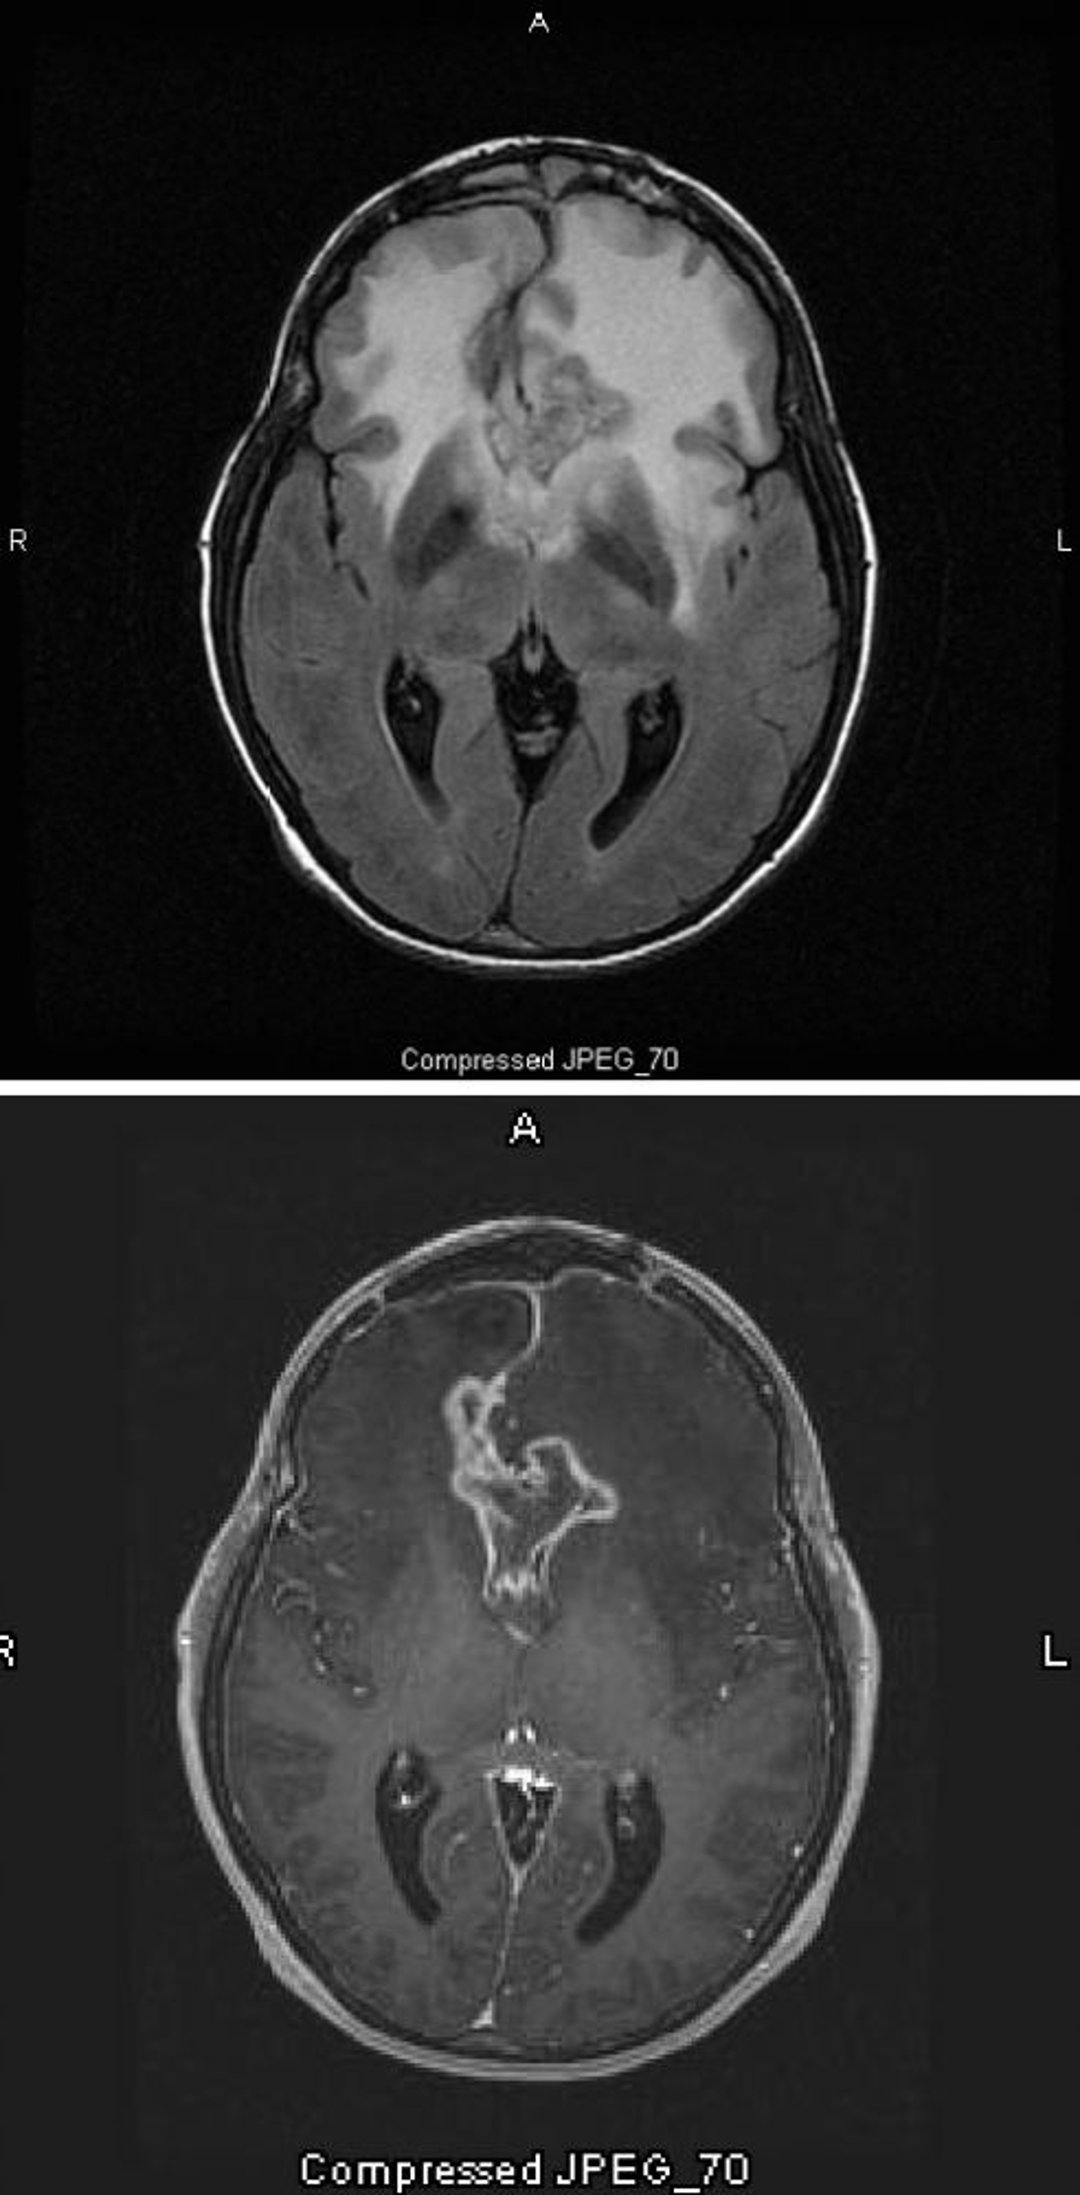

Phim chụp MRI T2-FLAIR (trên) cho thấy tín hiệu màu trắng lớn, hai bên (tăng mật độ) xung quanh u nguyên bào thần kinh đệm, đây là loại u sao bào ác tính nhất và mức độ cao nhất. U nguyên bào thần kinh đệm đặc biệt này được gọi là u thần kinh đệm dạng bướm vì tín hiệu màu trắng xung quanh khối u tạo thành cánh của con bướm; nó là do phù não. Trên hình ảnh chụp cắt lớp theo trọng số T1 (dưới), chất cản quang vạch ra rìa của khối u (ngấm thuốc hình vòng). Phù nề xuất hiện dưới dạng một vùng tối (giảm đậm âm) trên T1.

Hình ảnh do bác sĩ William R. Shapiro cung cấp